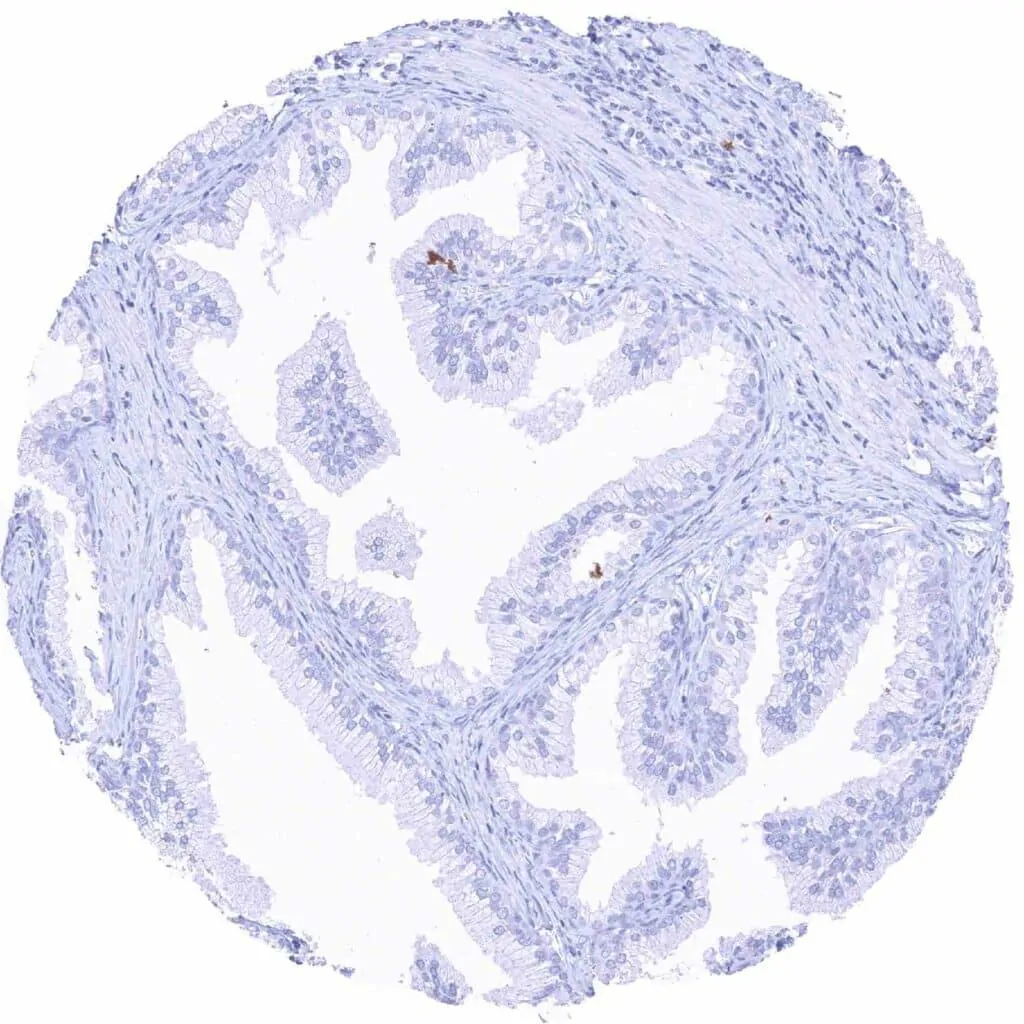

Prostate